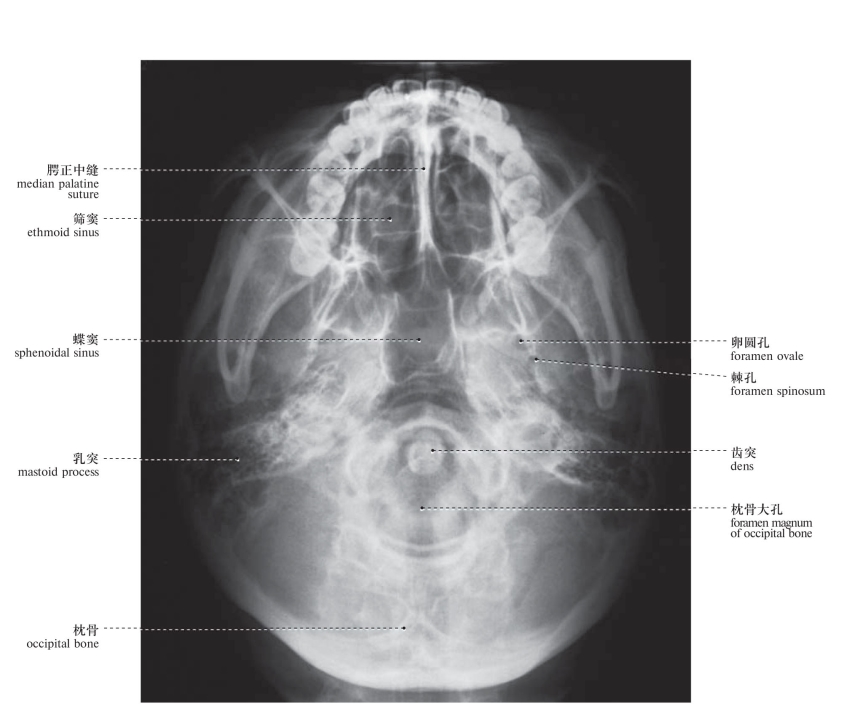

图50 颅X线像(下颌顶位)

Radiograph of the base of the skull (SMV)